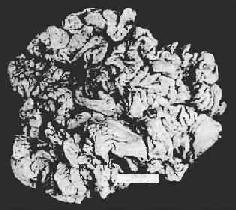

图10-4 胃粘膜肠上皮化生

胃粘膜上皮出现多量充满粘液的杯状细胞

3.肥厚性胃炎(hypertrophic gastritis) 又称肥厚性胃病(hypertrophic gastropathy)、Menetrier病。发病原因不明。病变特点是,粘膜肥厚,皱襞加深变宽似脑回状(图10-5)。镜下,腺体肥大增生,腺管延长。粘膜固有层炎性细胞浸润不显著。粘膜表面粘液分泌细胞数量增加,壁细胞及主细胞有时减少。临床上,多数患者有胃酸低下及因蛋白由胃液丧失而致的低蛋白血症。

图10-5 慢性肥厚性胃炎

胃粘膜肥厚,皱襞加深变宽似脑回状